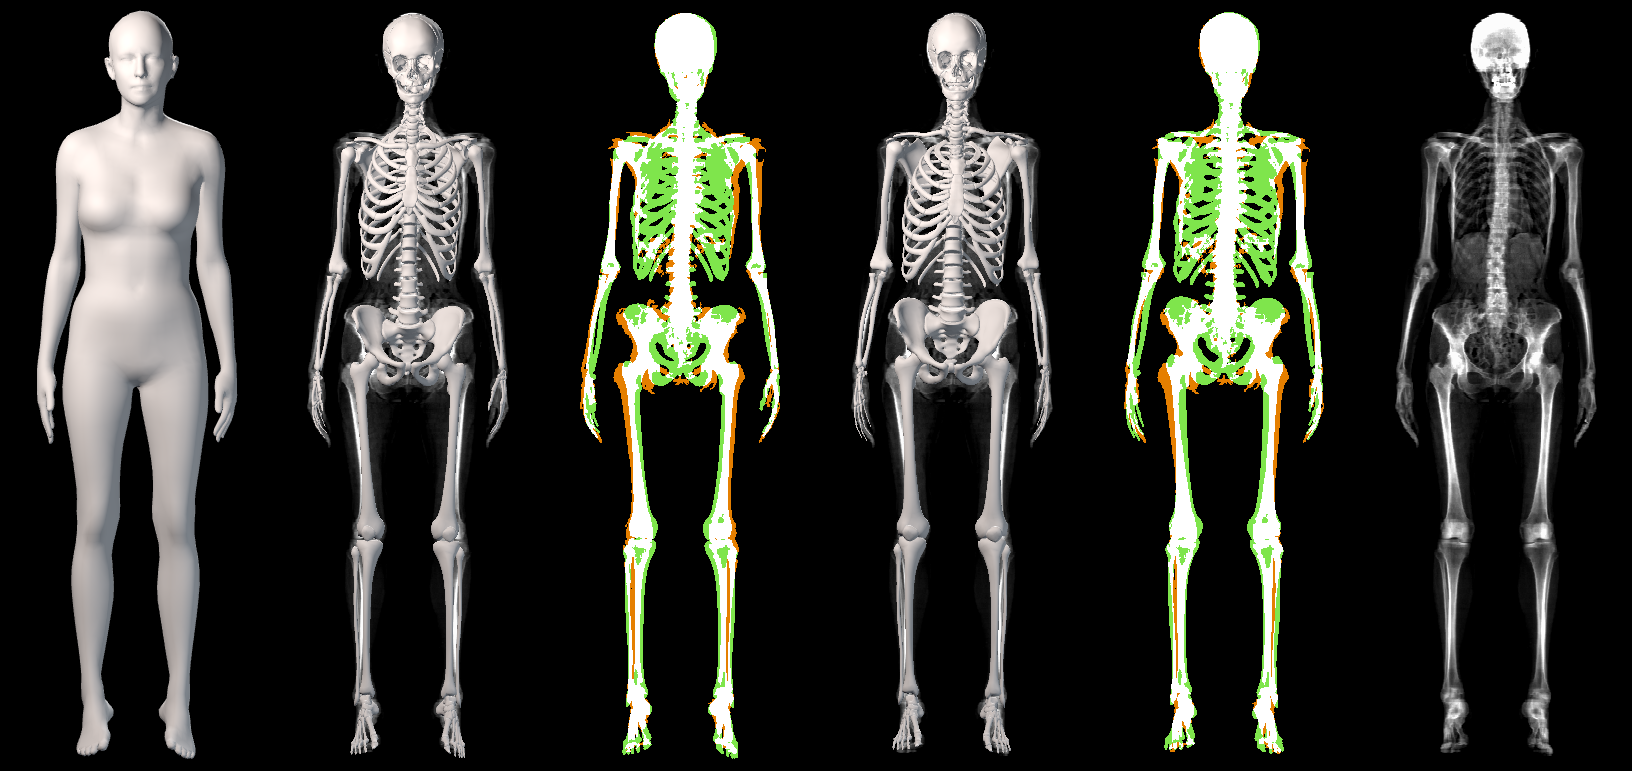

The presented metric has a limitation: predicting all the skin volume as bone would obtain a perfect result (, ). In Fig. 4 and Sup. Mat. we show that visually, OSSO’s predictions are coherent and match the DXA bone images better than Anatomy Transfer. In Sup. Mat. we provide examples of subjects with high Body Mass Index, for which Anatomy Transfer predicts a stretched skeleton, while ours are closer to the DXA skeleton mask.

In Figure 19, we present a qualitative comparison between our OSSO predictions and the ones from Anatomy Transfer. This results complement Sec. 5.3 of the main document.

From the DXA test set, we select 5 subjects spanning the dataset BMI distribution. From the skin alignment , we infer the skeleton and compare it to the subject’s skeleton DXA image. We denote the skeleton inferred with AT and the skeleton inferred with OSSO. is the mask rendered from the mesh .

As can be seen from the images, our predictions do better capture the global shape of the skeletons. Particularly, Anatomy Transfer often estimates the location of the hips to be too low with respect to the actual hips location. Our method predicts a skeleton which is visually closer to the one observed in the DXA images.